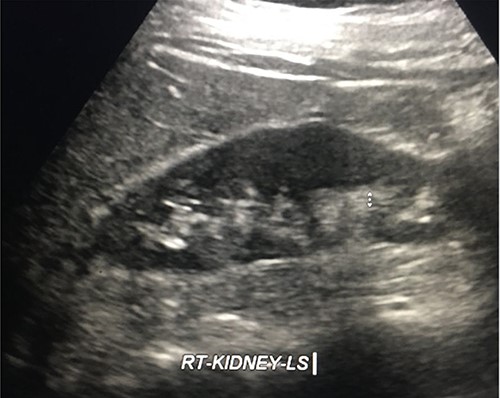

Three months later, the Urology department performed a retrograde ureteric stent exchange. Five months later, IR removed the ureteric stent via a retrograde approach. Retrograde ureterogram showed a fully healed, intact ureter. The ureteric stent was therefore not replaced. Three months later, follow-up ultrasound (US) showed no evidence of the obstruction (Fig. 10).

DISCUSSION